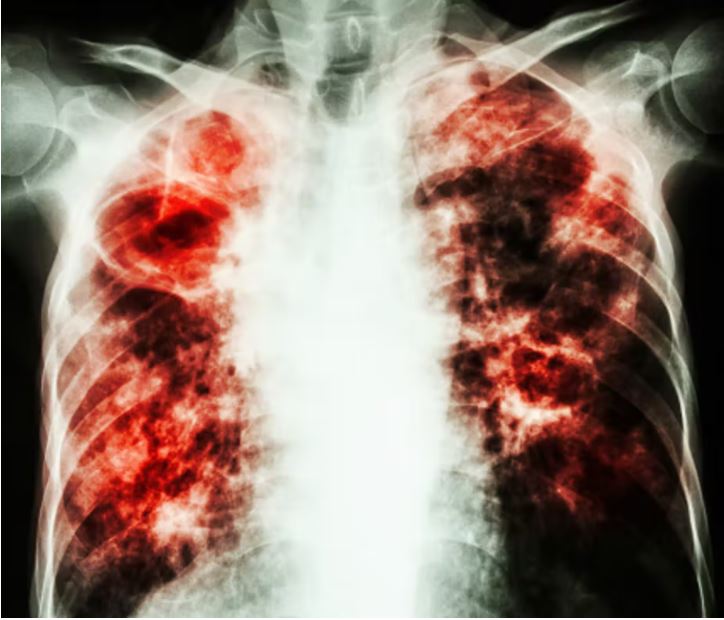

एक्स-रे कराने पर फेफड़ों में दाग-छिद्र होना

अगर अपने कभी एक्स रे कराया है और अगर फेफड़े में दाग या छिद्र नज़र आ रहा है तो सम्भव है कि टीबी हो, में अपने डॉक्टर से तुरंत कंसल्ट करते हुए परामर्श लें.